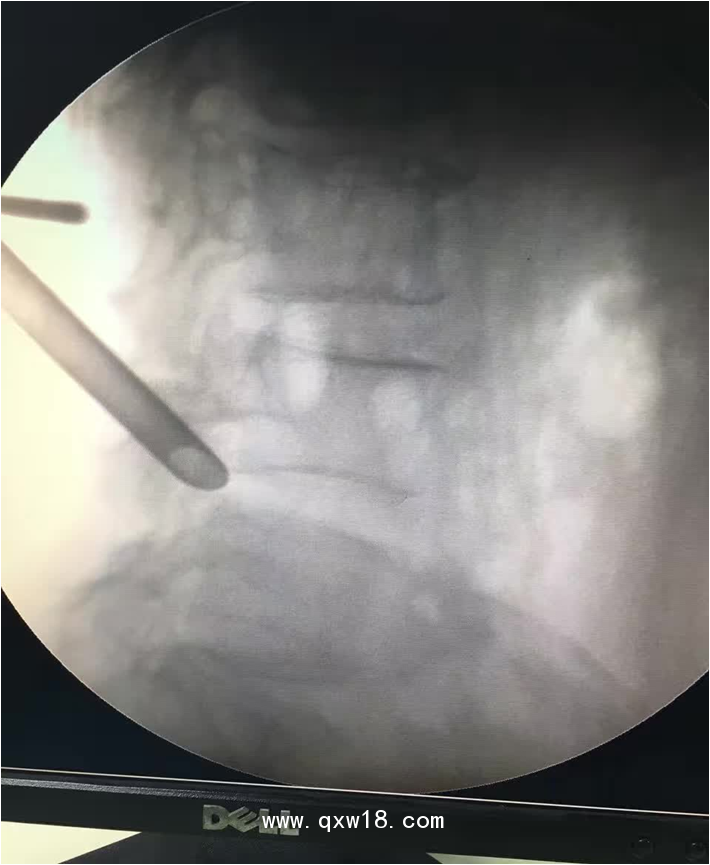

椎間孔鏡品牌椎間孔鏡椎間孔鏡技術椎間孔鏡培訓產(chǎn)品說明:

portant; word-wrap: break-word !important;">椎間孔鏡手術圍手術期注意事項: